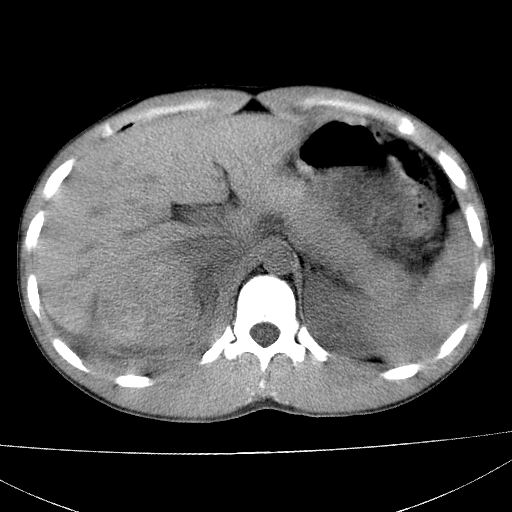

标题: CT15860:男,21岁,腹部外伤2小时伴胸疼。 [打印本页]

标题: CT15860:男,21岁,腹部外伤2小时伴胸疼。

1)肝破裂伴腹腔积液(血)。2)右肾破裂伴右肾包膜下及肾周血肿。3)腹部空腔脏器穿孔可能。4)右侧少量胸腔积液(血)。

肝、右肾包膜下血肿,右侧腰大肌及腹膜后血肿;腹腔少量积血;腹腔疑有少量游离气体伴肠破裂。

肝右肾挫裂伤,右肾包膜下及肾周血肿.胸腹腔少量积液.脾脏下部密度稍不均,必要时,增强.